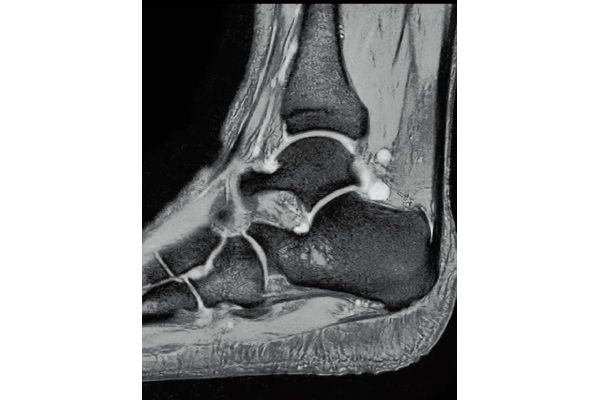

3D Bone

0.93×0.93×1.2(0.6)mm

1.1×1.1×1.2(0.6)mm

3D Balanced SARGE

with Phase Cycling,

0.93×0.70×1.0(0.5)mm, 1:44